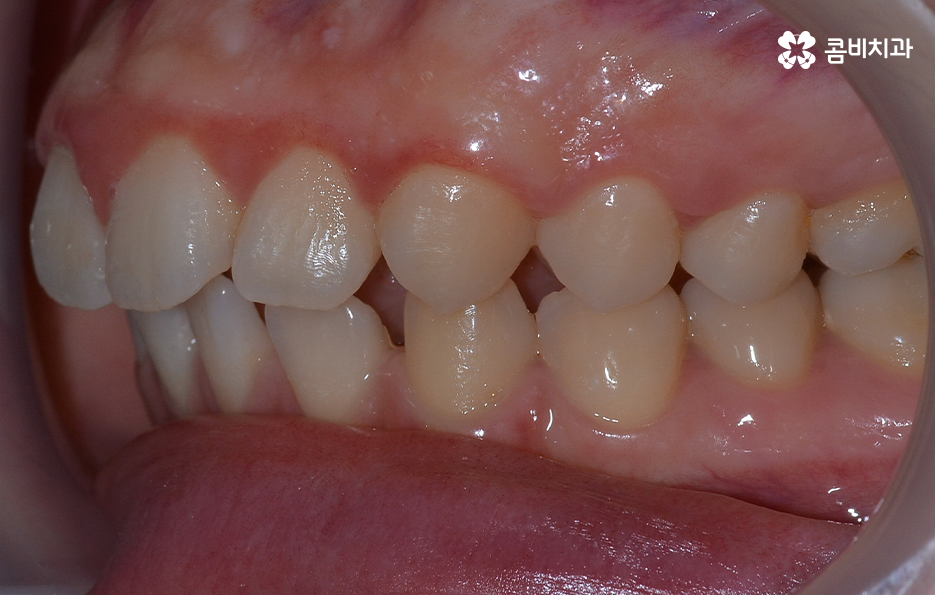

오늘 소개드릴 케이스의 경우 아랫니가 비교적 작기 때문에 교정을 통해 모아주고 윗니의 경우 측면으로 볼 때 더 잘 느껴지겠지만 다소 돌출된 상태이기 때문에 윗니는 발치를 통해 치아 이동 공간을 확보하여 돌출된 앞니를 안쪽으로 모아준 사례로 볼 수 있는데요

아랫니의 경우 치아 사이가 벌어져 있기 때문에 치아를 이동시킬 수 있는 공간이 이미 확보된 상태이고 윗니는 다소 돌출된 앞니를 안쪽으로 들어오게 하면서 심미선을 얼굴형에 조화롭게 맞출 수 있으며 그와 동시에 윗니와 아랫니의 교합도 고려한 치료 계획을 세운 것으로 간단하게 말씀드릴 수 있어요